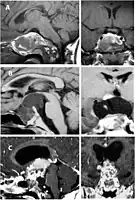

Imaging scans for craniopharyngioma

A physician can conduct a few scans and tests to diagnose a person with craniopharyngioma.[19] High-resolution magnetic resonance imaging (MRI) is valuable because it allows the neuroradiologist to view the tumor from different angles.

In some cases, a powerful 3T (Tesla) MRI scanner can help define the location of critical brain structures affected by the tumor. The histologic pattern consists of nesting of squamous epithelium bordered by radially arranged cells. It is frequently accompanied by calcium deposition and may have a microscopic papillary architecture. A computed tomography (CT) scan is also a good diagnostic tool, as it detects calcification in the tumor.[20]

In the adamantinomatous type, calcifications are visible on neuroimaging and are helpful in diagnosis.

The papillary type rarely calcifies. A vast majority of craniopharyngiomas in children are adamantiomatous, whereas both subtypes are common in adults. Mixed-type tumors also occur.[24]

On macroscopic examination, craniopharyngiomas are cystic or partially cystic with solid areas. On light microscopy, the cysts are seen to be lined by stratified squamous epithelium. Keratin pearls may also be seen. The cysts are usually filled with a yellow, viscous fluid rich in cholesterol crystals. Of a long list of possible symptoms, the most common presentations include headaches, growth failure, and bitemporal hemianopsia.

CT scan showing a craniopharyngioma

Enhanced T1 weighted MRIs of craniopharyngiomas

Micrograph showing the characteristic features of an adamantinomatous craniopharyngioma - cystic spaces, calcifications, and "wet" keratin, HPS stain

Micrograph showing a papillary craniopharyngioma, HPS stain